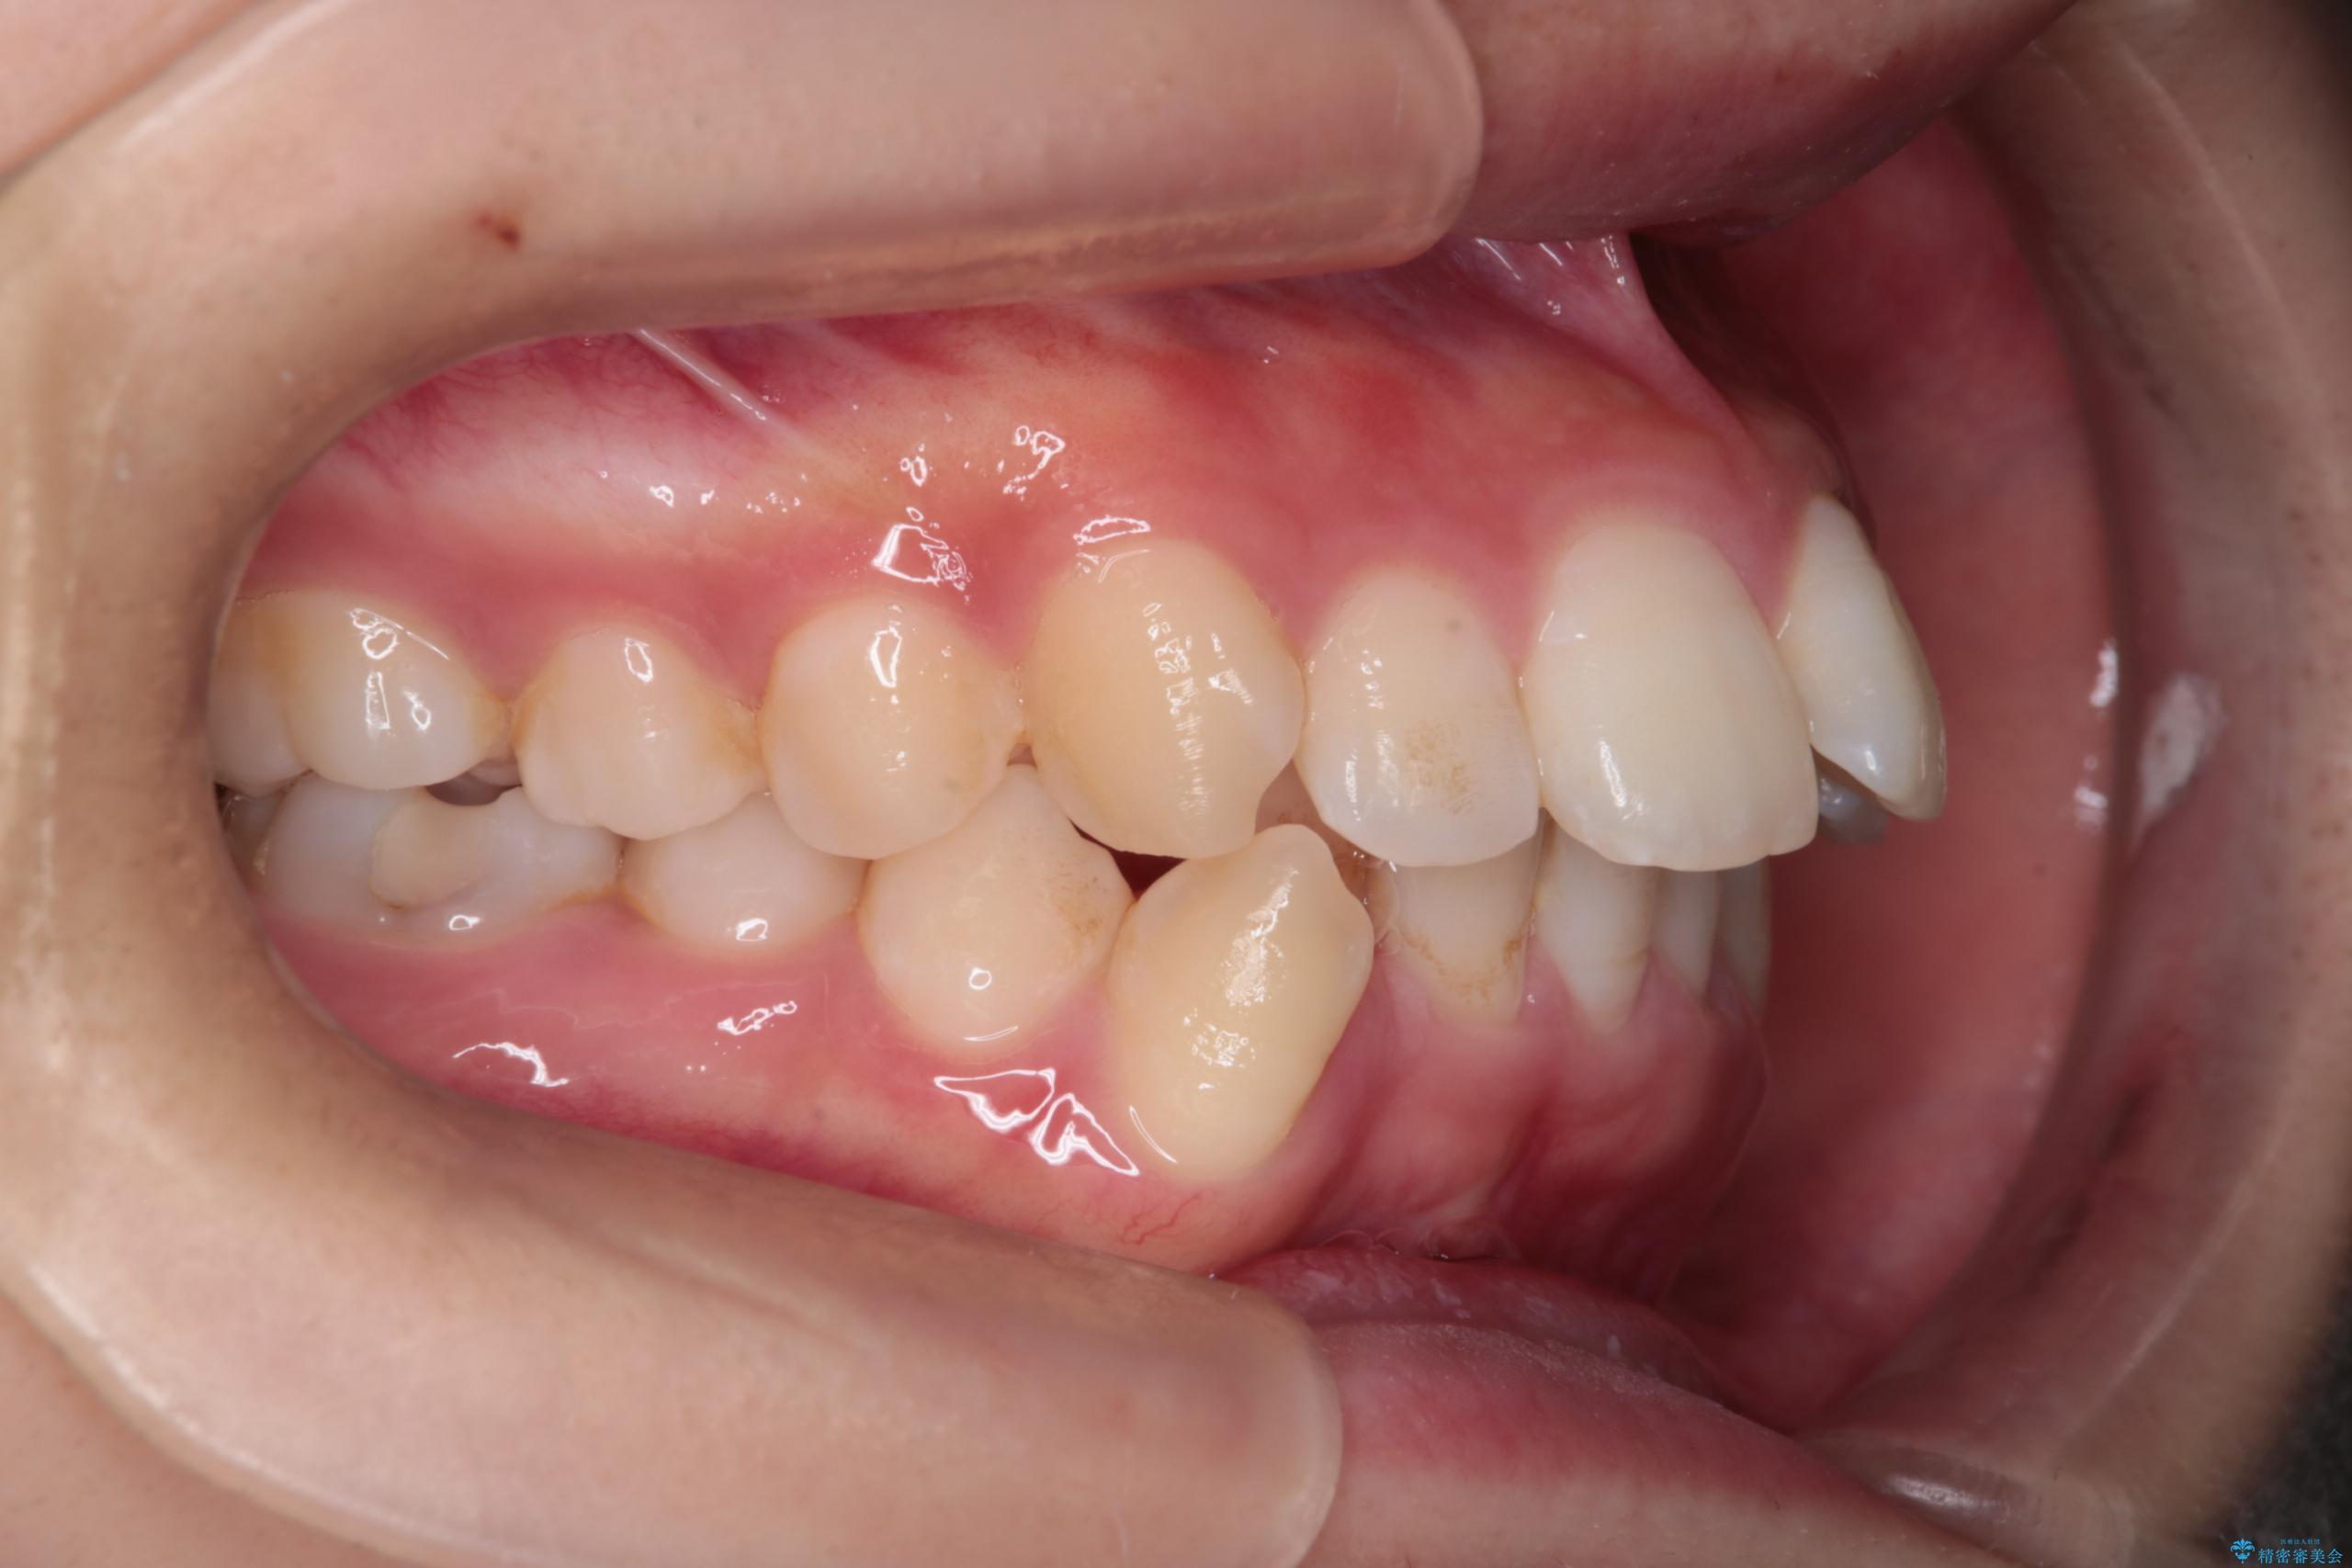

- 前歯から奥歯にかけて歯の重なりが激しい歯のがたつき(重度叢生)を主訴にご来院されました。精密検査の結果、歯が並ぶスペースが大幅に不足しており、歯並びを整え、口元を美しく引っ込めるためには、スペースの確保が必要と診断しました。そこで、上下左右の第一小臼歯(4番目の歯)を計4本抜歯し、そのスペースを利用して歯並び全体を整える抜歯矯正の治療計画を立案。装置には、透明で目立たないインビザラインを採用し、審美性と治療効果の両立を目指しました。

今回の治療では、重度の叢生を改善するため、まず計画通り上下左右4本の小臼歯を抜歯し、歯を並べるための十分なスペースを確保しました。装置には透明で取り外し可能なインビザラインを使用。抜歯によってできたスペースを最大限に活用し、マウスピースを定期的に交換しながら、デコボコを解消しつつ、前歯を効果的に後退させました。

治療の結果、長年の悩みであった重度の歯のがたつきが解消され、口元の突出感も改善。機能的にも安定し、審美的にも美しい、理想的な歯並びを獲得していただけました。